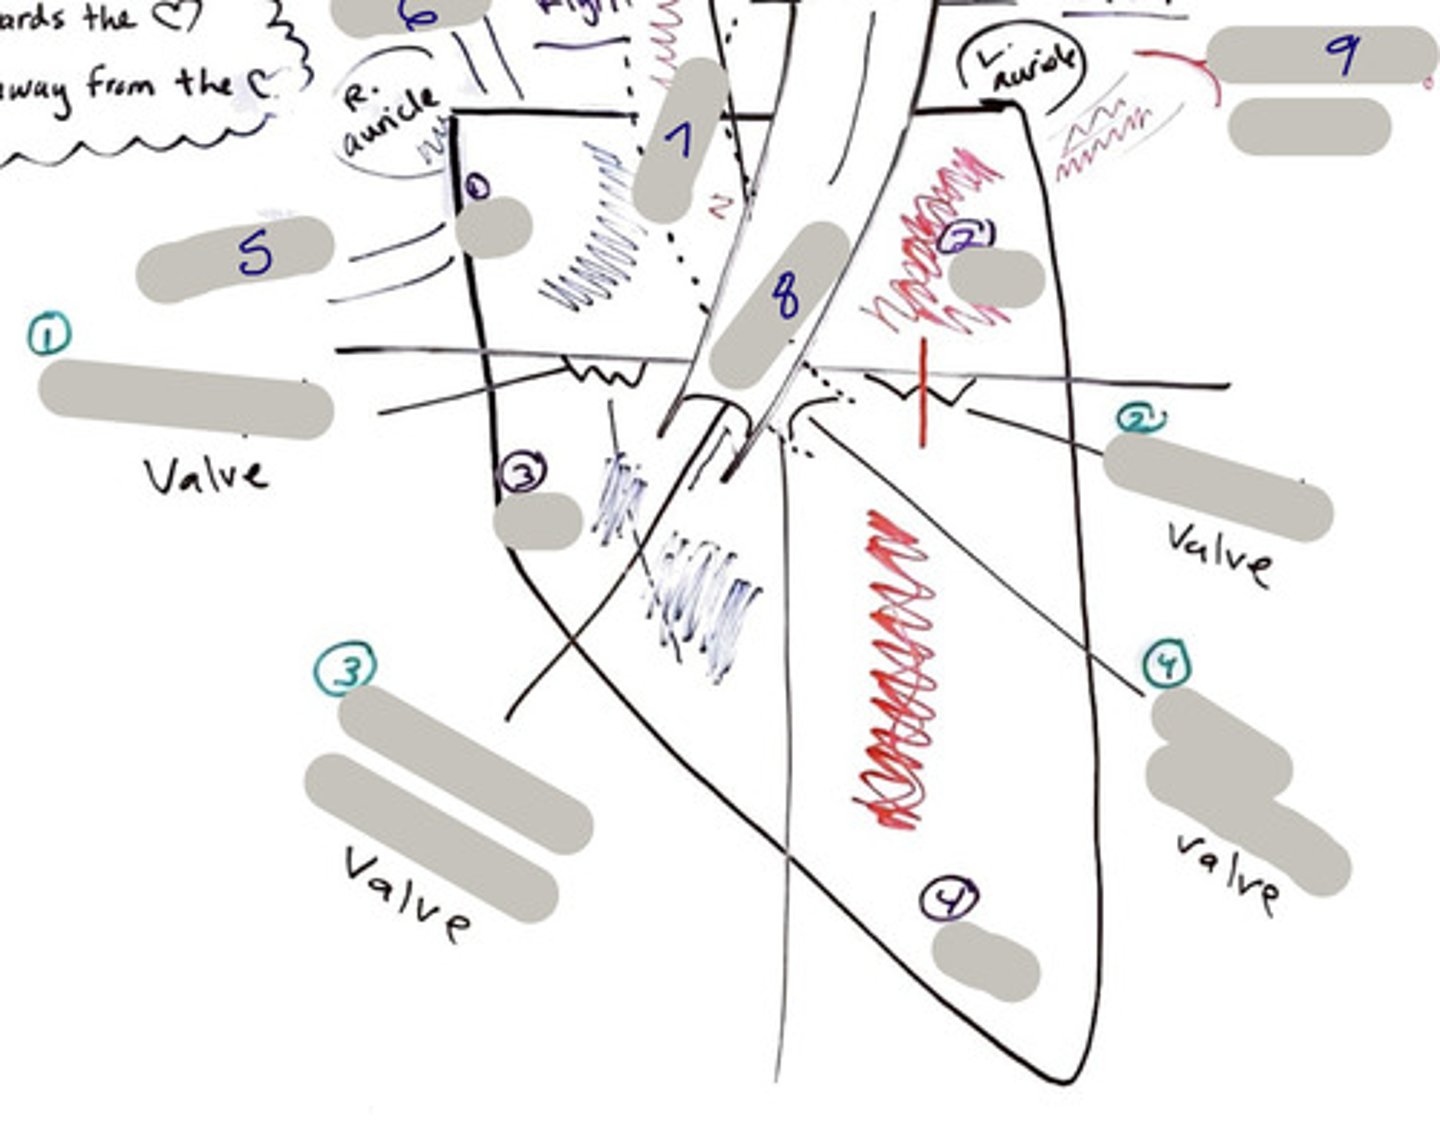

Tricuspid Valve (Right Atrioventricular Valve)

1-valve

Bicuspid valve (Left Atrioventricular Valve)

2-valve

Pulmonary Semilunar Valve

3-valve

Aortic Semilunar Valve

4-valve

Right Atrium

1-chamber

Left Atrium

2-chamber

Right Ventricle

3-chamber

Left Ventricle

4-chamber

Inferior Vena Cava

5-A vein that is the largest vein in the human body and returns blood to the right atrium of the heart from bodily parts below the diaphragm.

Superior Vena Cava

6-A vein that is the second largest vein in the human body and returns blood to the right atrium of the heart from the upper half of the body.

Aorta

7-The large arterial trunk that carries blood from the heart to be distributed by branch arteries through the body.

Pulmonary Trunk

8-carries blood from right ventricle to pulmonary arteries

Pulmonary veins

9-a vein carrying oxygenated blood from the lungs to the left atrium of the heart.